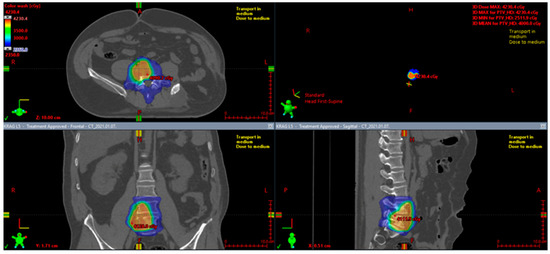

7.2. Perioperative Radiotherapy

- Gao, C.; Zhang, Y.; Jing, M.; Qu, W.; Li, J.; Zhao, X.R.; Yu, Y.H. Postoperative Radiotherapy for the Treatment of Solitary Fibrous Tumor With Malignant Transformation of the Pelvic: A Rare Case Report With Literature Review. Medicine 2016, 95, e2433. [Google Scholar] [CrossRef] [PubMed]